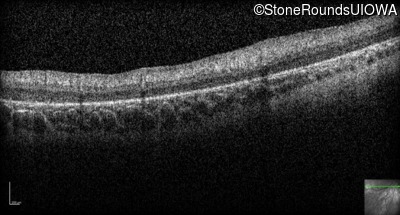

Optical Coherence Tomography - Right -

No Light Perception

Exemplar

Optical Coherence Tomography - Left -